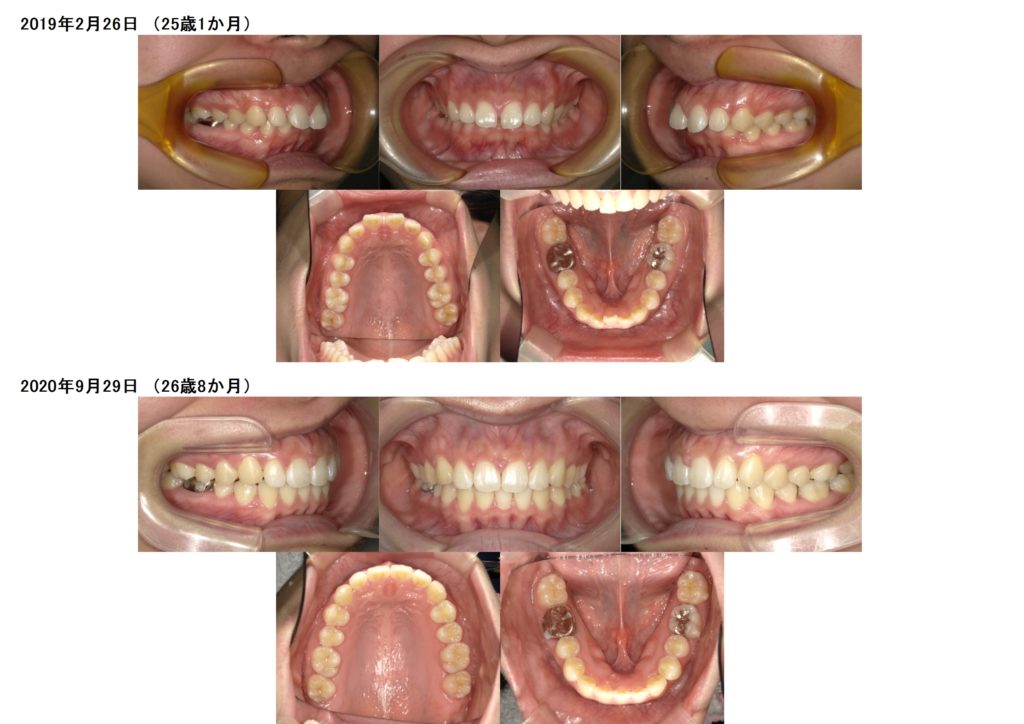

↑この方は下の1番目の左側が1本先天性欠如です。

診断例としては抜歯をせず、中心がピッタリとあいませんが、骨の正中など考慮し他の歯を抜歯せずに治療します。

上顎前突(上の顎が突出)なのが写真を見て分かります。

初めからインビザラインのマウスピースを使用し治療を開始しました。

約1年ほどで、噛み合わせ、上の歯の隙間、前突部分、上下のアーチがここまで変化したのが分かると思います。

↑下の写真で上の前歯から数え3番目の歯に左右透明のボタンを装着し、ここから噛み合わせの微調整を開始します。

治療前、治療後のお写真を比較してみるととってもキレイになりましたよね☆